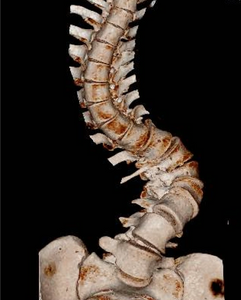

Diagnosis, from history, examination and imaging, helps advise on natural history, provide reassurance and outline potential treatment strategies for the whole range of spinal conditions. Scanning can help to rule out problems but standing X-rays in some patients are sometimes invaluable as we see the spine under load

Mr Harding undertakes all aspects of spinal surgery, from microsurgery through to complex reconstruction in adults and children for spinal deformity in all regions of the spine. Specific details can be found in 'Conditions' and 'Treatments'

You may just want reassuring or further explanation for a complex problem. Having a second opinion can help you make your decision. Mr Harding has a worldwide reputation and expertise in adult deformity and can provide a remote second opinion service remotely to patients worldwide. Please contact PA to arrange this